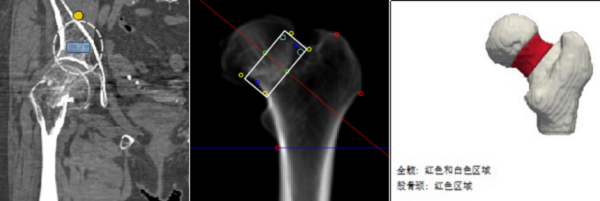

案例二:另一位老人家摔伤髋部,检查发现髋部骨头密度很低,同样达到“严重骨质疏松”诊断。这帮助医生和家人意识到,问题不仅是摔伤,更是骨头本身变脆了,后续需要系统性的骨骼健康管理。

ScreenShot_2025-12-05_173338_779

图片8